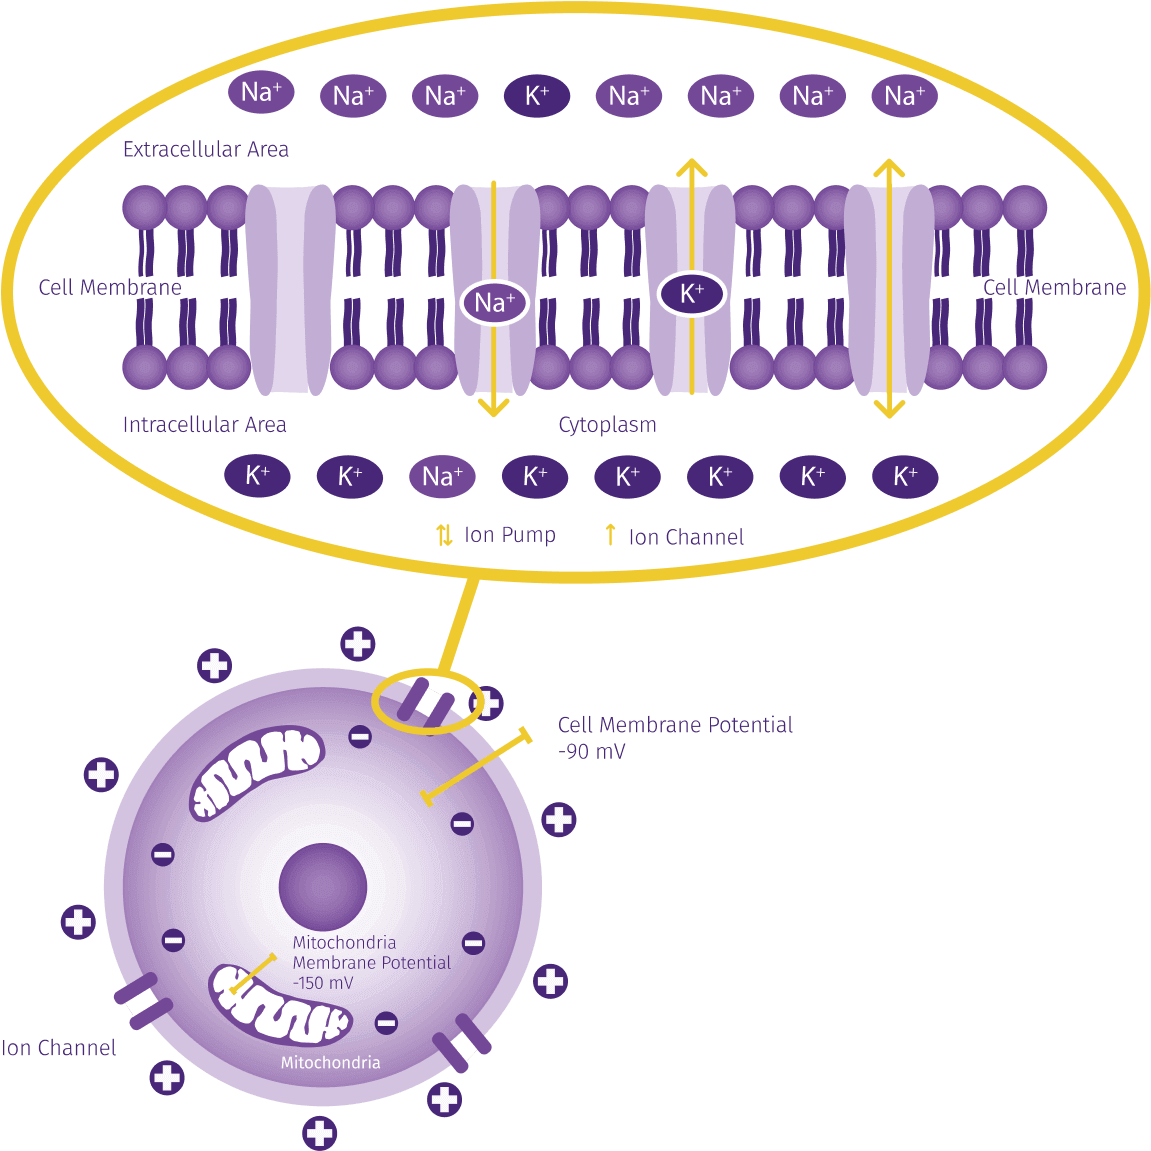

Terve solu tarvitsee riittävän solukalvojännitteen (noin -70 mV – -90 mV) ylläpitääkseen säätelyprosessejaan. Kaikilla sairauksilla ja vammoilla on yksi yhteinen piirre: sairastuneilla soluilla ei enää ole lainkaan tai vain osittain oma luonnollinen solukalvopotentiaali.

Ioni-induktiokenttä stimuloi heikentyneet kehon solut ja nostaa niiden terveen jännitepotentiaalin. Solu voi jatkaa säätelyprosesseja, vaihtaa hivenaineita ja tuottaa vastaavia energiamolekyylejä.

TÄRKEÄÄ: Ainoastaan solut, joiden kalvopotentiaali on laskenut, reagoivat Pulssit Ion-Induction-menetelmään. papimi ei aiheuta solujen lämpötilamuutoksia.

Ioni-induktiohoito nostaa solun kalvopotentiaalia sekä solun että mitokondrioiden potentiaalia.

Terve solukalvojännite mahdollistaa ioninvaihdon kalvoproteiinien kautta ja tukee solun optimaalisesta toiminnasta ja energiansaannista vastaavia biokemiallisia säätelykaskadeja .

Terve solu tarvitsee riittävän solukalvopotentiaalin (noin -70mV – -90mV) ylläpitääkseen säätelyprosessejaan. Jos jännite laskee, se voi aiheuttaa kipua, tulehdusta, turvotusta tai sepelvaltimotaudin sekä muita patologioita. Ioni-induktiokenttä stimuloi heikentyneet kehon solut ja nostaa ne terveeseen jännitepotentiaaliinsa.

Solu voi jatkaa säätelyprosesseja, vaihtaa hivenaineita ja tuottaa vastaavia energiamolekyylejä.